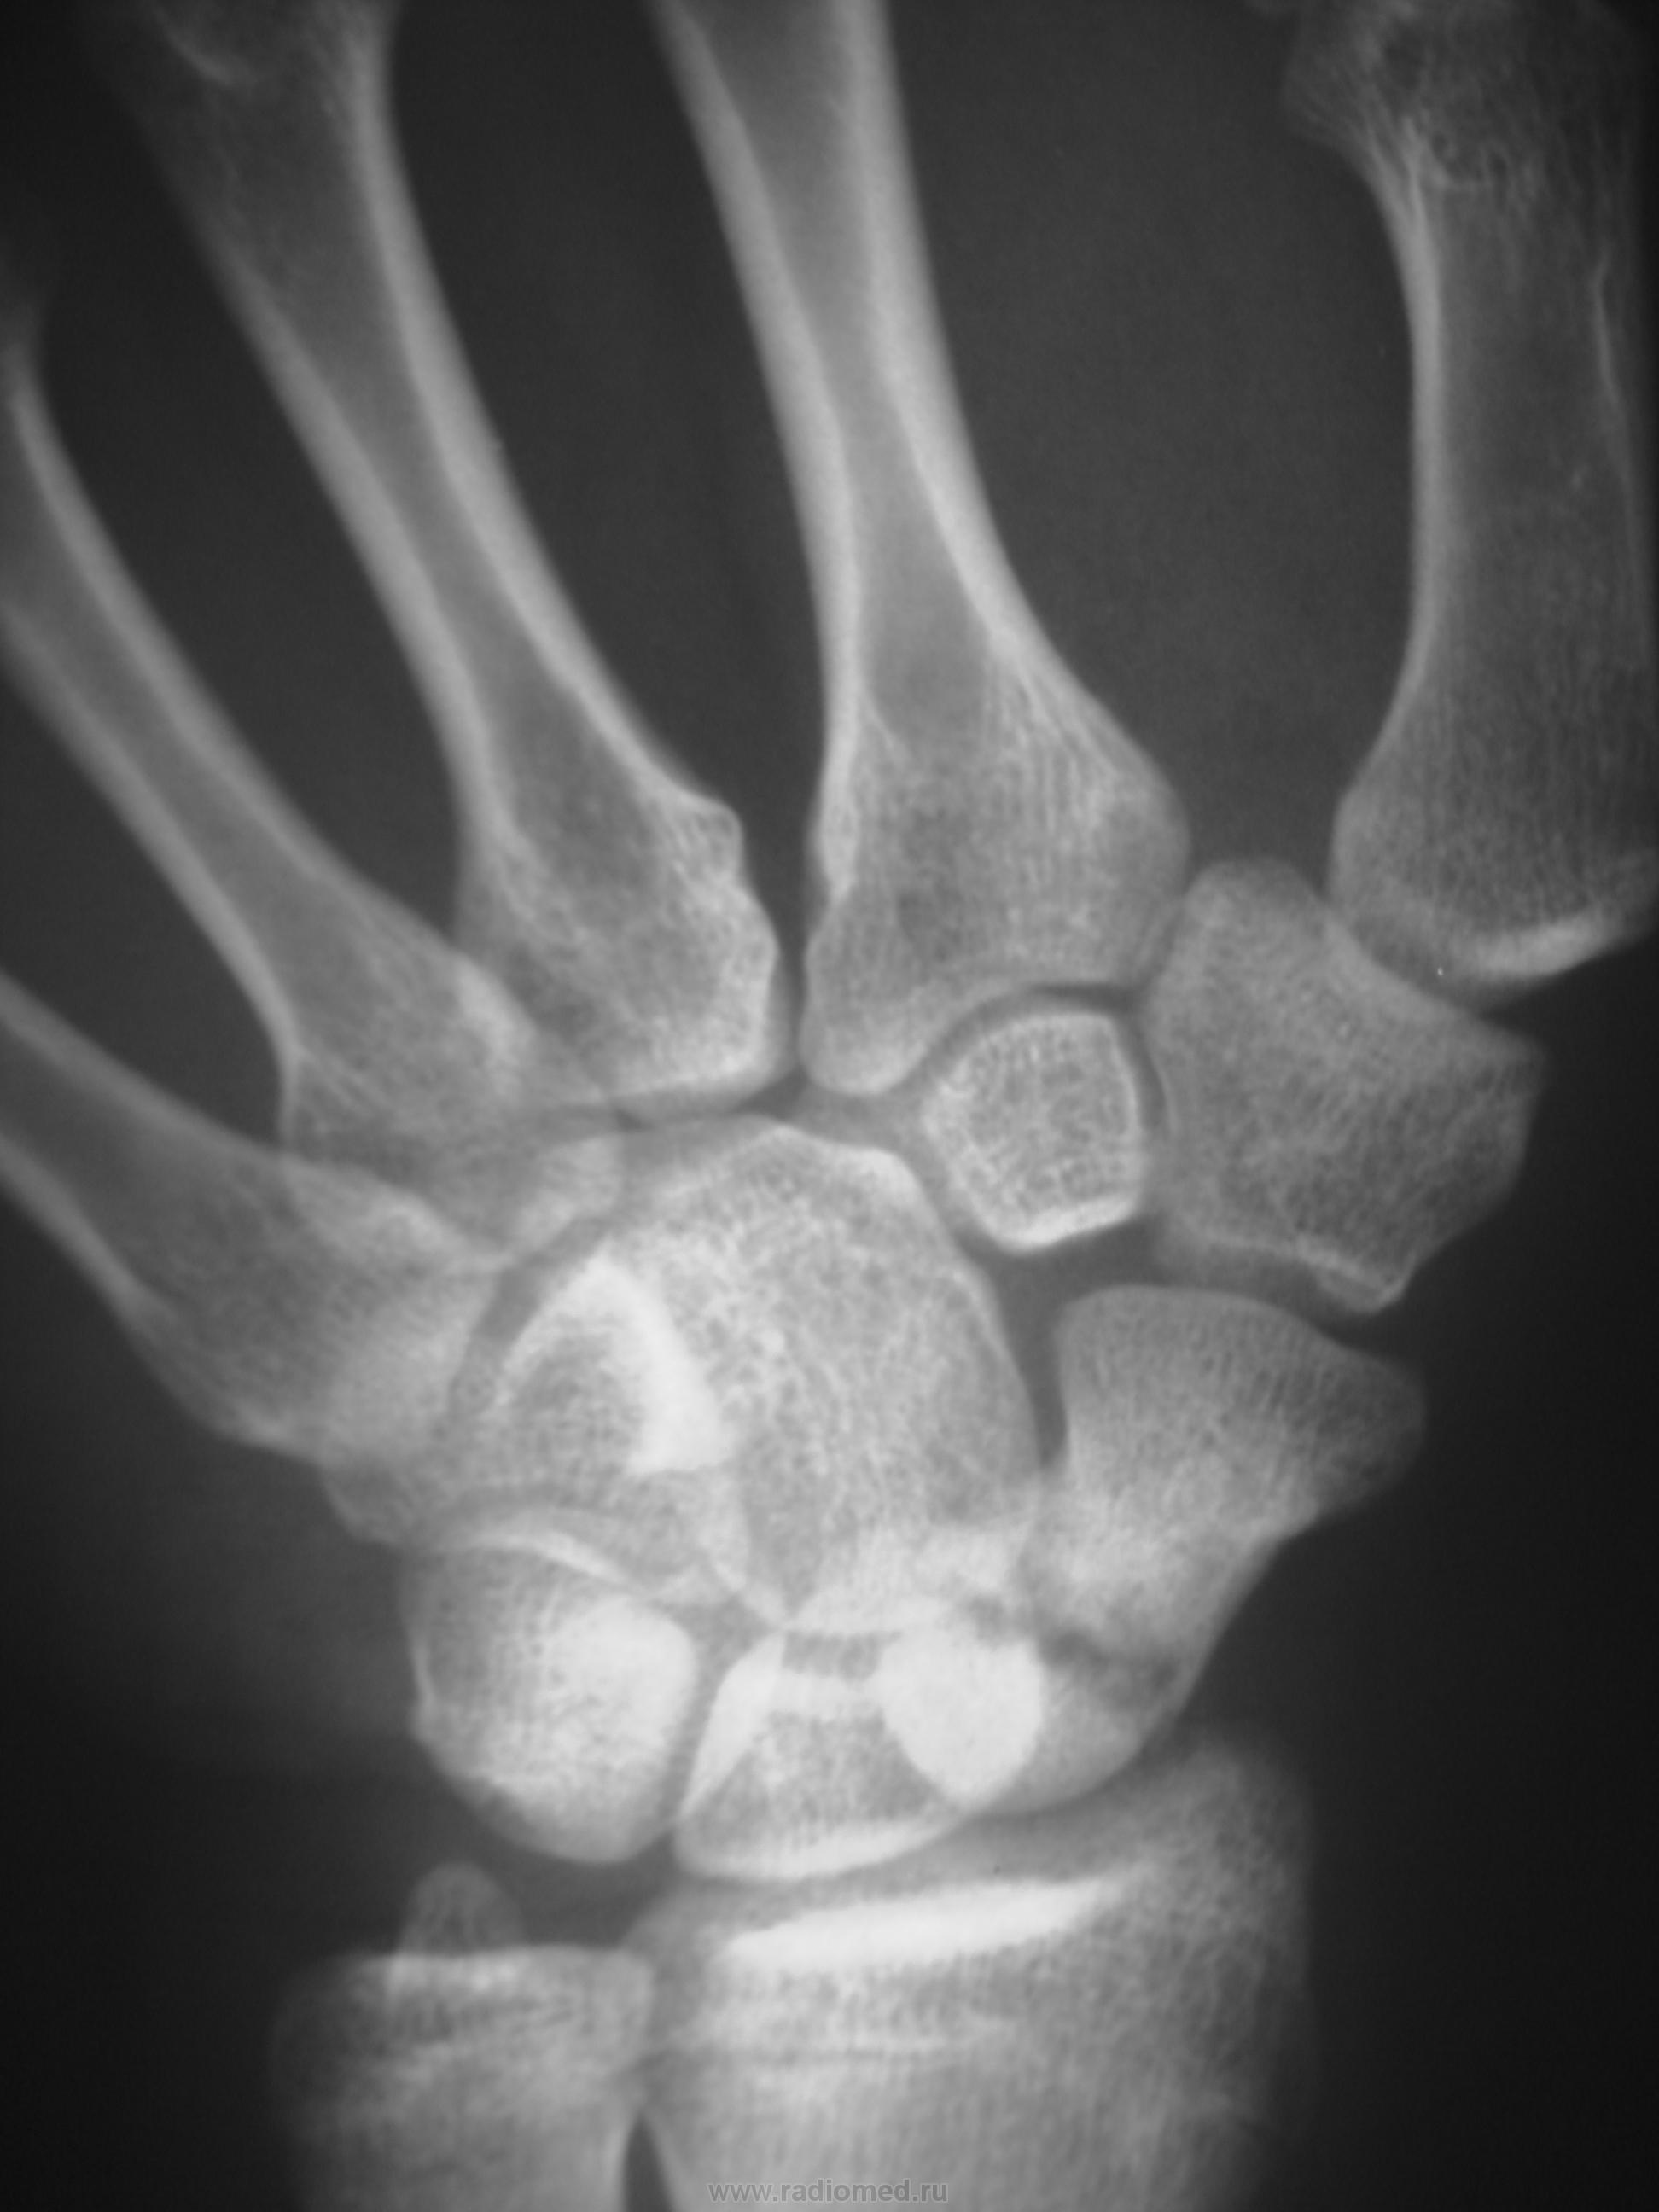

Травма в октябре 2009,сейчас появились боль, припухлость в обл. ладьевидной кости. Какие будут мнения, уважаемые коллеги?

Значит в октябре не болело. Это странно. Несросшийся перелом есть. А вот псевдартроз как-то не очень... Здесь нужна проекция для ладьевидной кости, без наслоений других.

В  октябре само сабой болело,перелом был диагносцирован,ходил в гипсе, но через месяц сняли и носили ортез. Не болело до настоящего времени.

В наших условиях - знатоки говорят о необходимости операции чуть ли не в первые 2 часа после перелома, переломы ладьи никогда не срастаются...